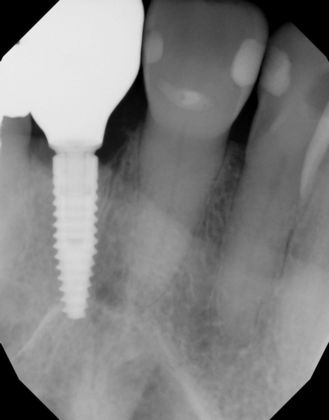

Dental Implants: Case 43

Upper front central incisor fractured and was replaced by an implant crown